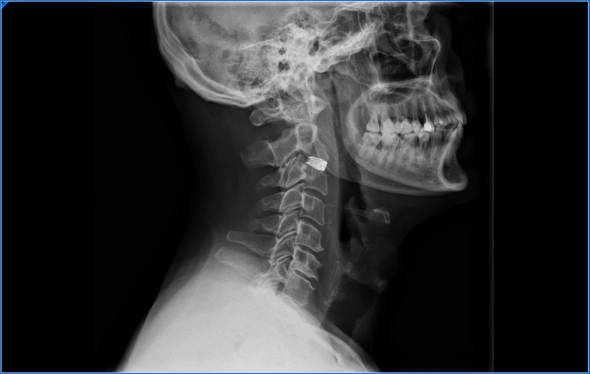

Los síntomas que nos describe el paciente y la exploración clínica debe hacernos sospechar que tenemos una hernia C5-C6. Una vez que tenemos un diagnostico de sospecha pediremos las pruebas necesarias para llegar al diagnóstico definitivo.

Resonancia magnética. Es la prueba que más información aporta. En la RMN veremos si efectivamente tenemos una hernia C5-C6, veremos si la hernia estrecha el agujero por el que sale la raíz nerviosa o comprime la médula espinal.

Electromiograma. El elecromiograma nos sirve para determinar que raíz esta comprimida y si la compresión esta a nivel del disco C5-C6. Cuando vemos una resonancia podemos tener dudas del nivel en el que se está produciendo la compresión neurológica, es en estos casos cuando la electromiografía es más util pues nos puede indicar que raiz nerviosa es la que está afectada.